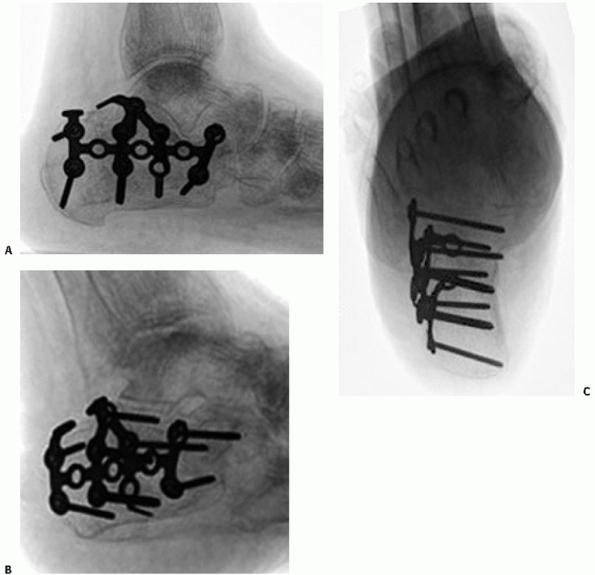

introduction of locking plate technology has been an important advance

osteopenic bone. Recently, several calcaneal locking plates have been

introduced. In cadaveric models, locked plates have generally increased

the stability of fracture fixation,213 with polyaxially locked screws performing best.176,178 One study showed no biomechanical advantage with locking plate fixation in a cadaver model of Sanders type IIB fractures.174

To date, no studies have demonstrated clinical superiority of locked

calcaneal plates to nonlocked, low-profile neutralization plates. The

indications for locking plates in the treatment of calcaneus fractures

are still being defined but may include use in highly comminuted

fractures, the elderly, or those with particularly poor bone stock (Fig. 59-28).